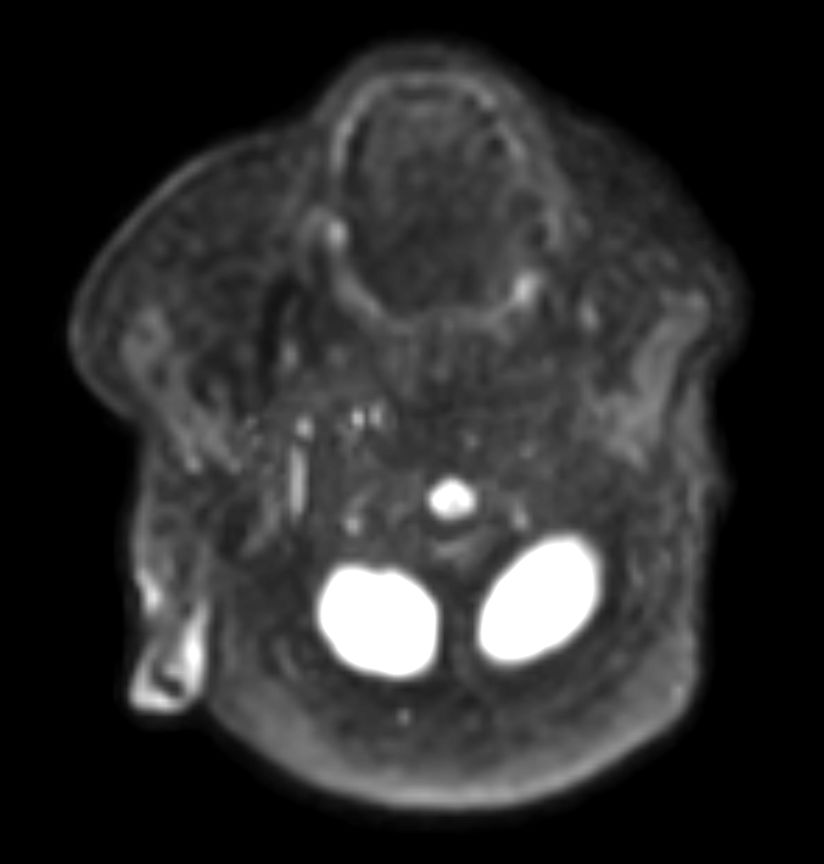

DWI TSE XD (b600)

DWI TSE XD (ADC)